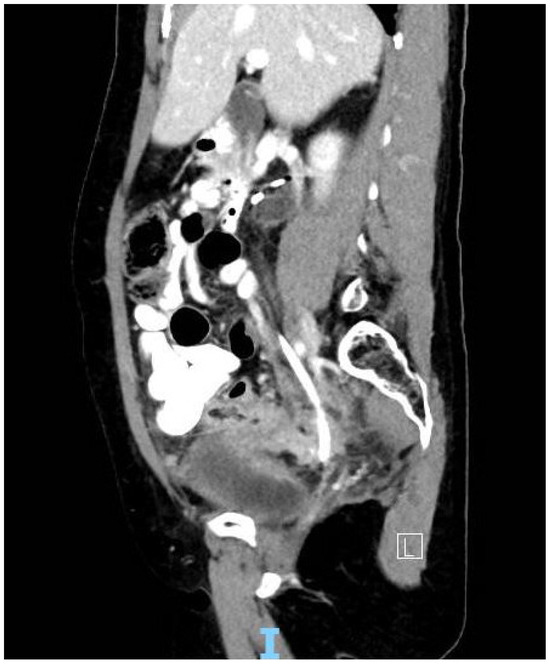

In patients such as the above, the role of MRI is multi- faceted, in that it is used for treatment planning, local staging, and for consideration of radical salvage surgery (for example, anterior or total pelvic exenteration, which is offered at this centre). As seen on this re-staging study, the artefact produced by the stainless steel cross- braiding component of the stent markedly compromises image quality, and with it, diagnostic certainty. A similar effect is not seen in CT imaging (Figure 2).

Figure 2.

CT of patient with Teleflex Rüsch DD Tumour Stent in situ.